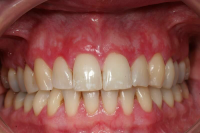

Gingivit är tandköttsinflammation som visar sig genom marginal blödning vid sondering, men där tanden ej har någon förlust av käkbensfäste.

Diagnosen gingivit används vid tänder med marginal inflammation och blödande tandkött, men ingen förekomst av marginal benförlust. Fickdjup 1–3 mm, pseudofickor kan förekomma upp till 5 mm.

Ödematös, rodnad och blödande gingiva.